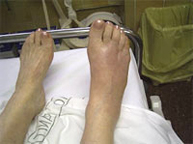

La región del pie es un conjunto de huesos y articulaciones con numerosas funciones entre las que destaca el soporte de todo nuestro peso y la deambulación (caminar). Es una región sometida a carga constantemente salvo cuando no caminamos, es por ello que su rápida recuperación es indispensable para poder desplazarnos de un lugar a otro. El pie a su vez se divide en tres partes: retropié, mediopié y antepié y cada región sufre sus lesiones características. En el deporte las lesiones del pie son muy frecuentes debido a la implicación de éste en la mayor parte de ellos. Por lo general las fracturas del pie responden correctamente al tratamiento conservador reservando la actitud quirúrgica a aquellas lesiones complejas irreparables sin cirugía.